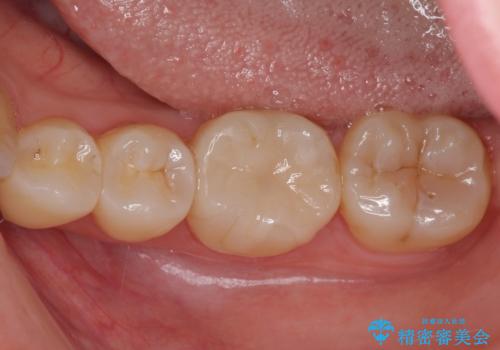

セラミックインレーを装着したことで、とても自然な仕上がりとなりました。

患者様も大きく口を開けても気にならなくなった、大変喜んでくださいました。